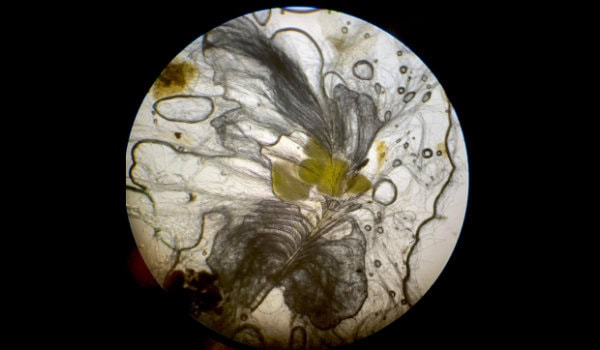

Ein modernes Mikroskop mit einer integrierten digitalen Kamera und einer hauseigenen Färbebank ermöglicht uns die Untersuchung von Blutausstrichen, Feinnadelaspirationen (FNA), dermatologischen Abstrichen und Geschabseln, sowie von Kot- und Urinuntersuchungen.